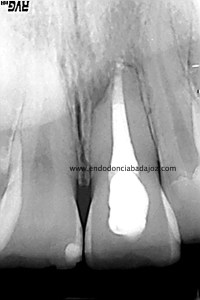

Una vez que hemos transportado y barrera apical, hacemos el backfilling con la Pistola Obtura II.

(Rx Mesioradial)                                                               (Rx Ortoradial)

La paciente fue llamada a revisión al año: